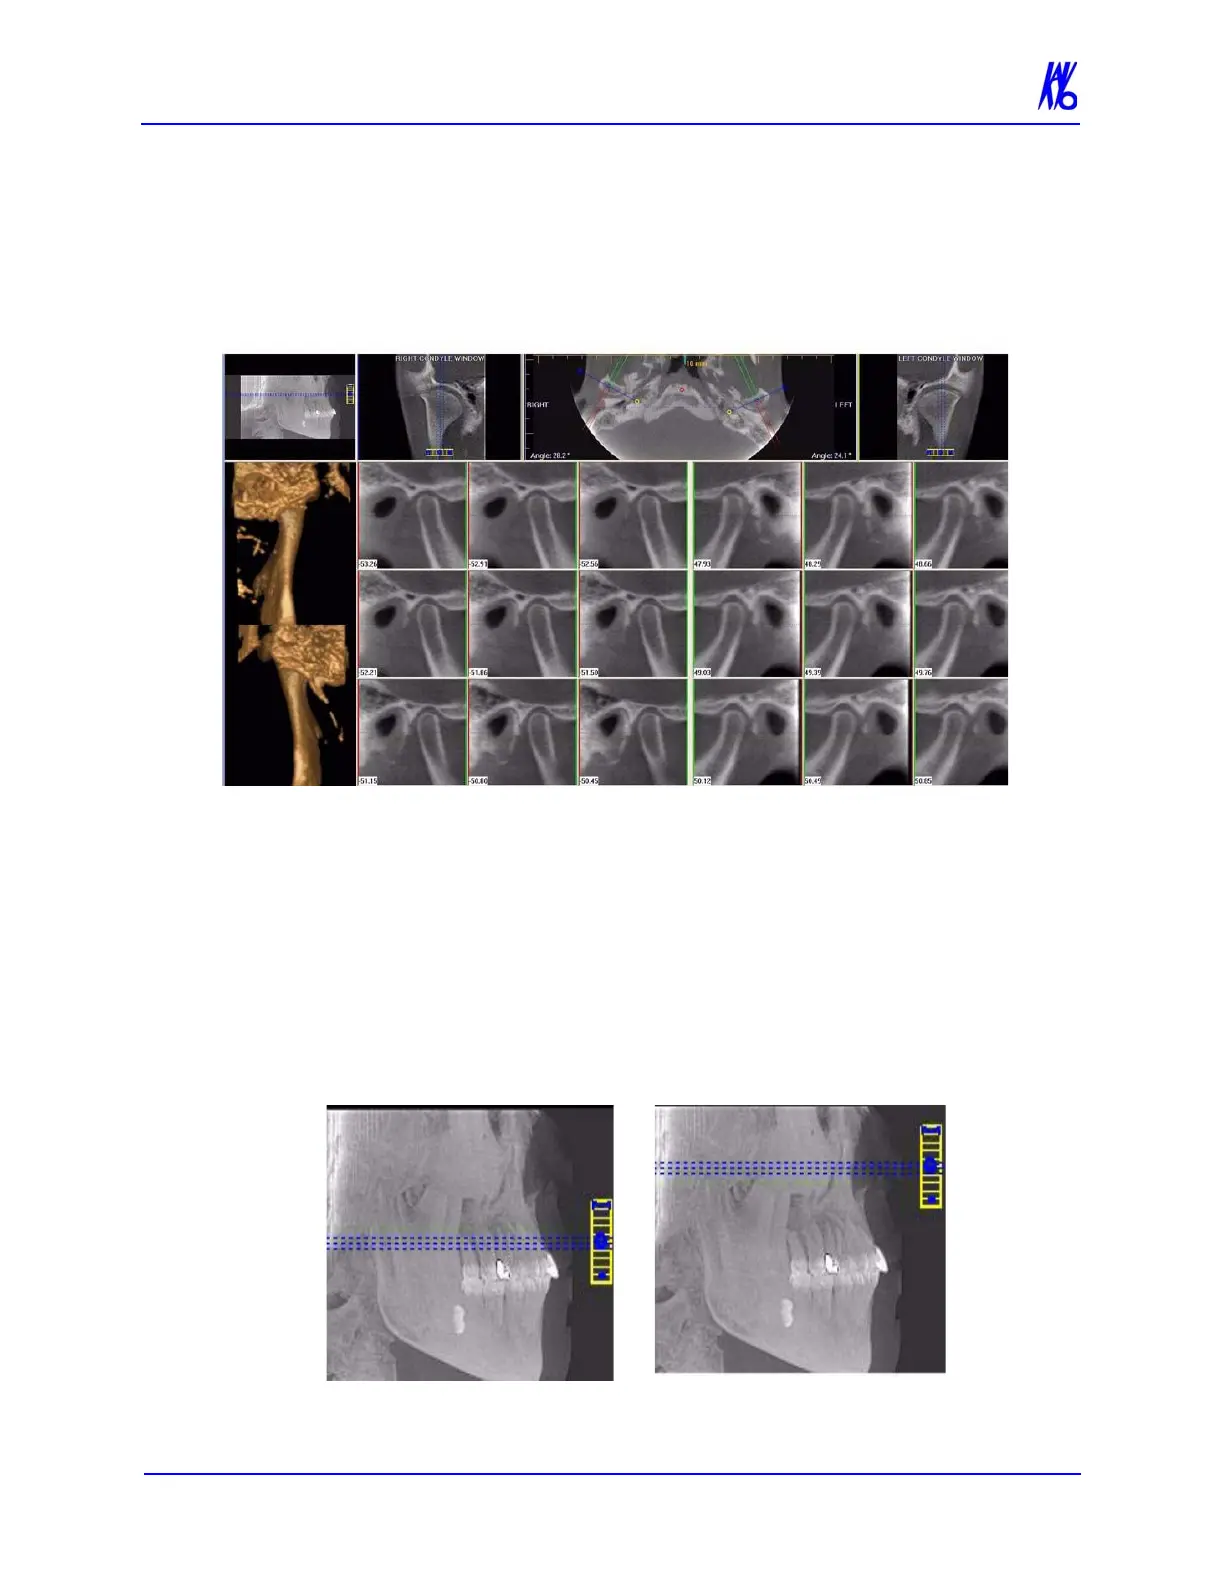

TMJ Screen

Double-clicking the Axial View on the Preview Screen displays the

TMJ Screen.

TMJ Screen enables condyle mapping and creating corresponding

coronal slice views.

To use the TMJ Screen:

1. If necessary, pan the Axial (SMV) View (upper left) down in the

window to see the condyles. (See Pan Feature.)

2. Use the scroll bar center (O) tool to locate the condyles for

proper mapping.